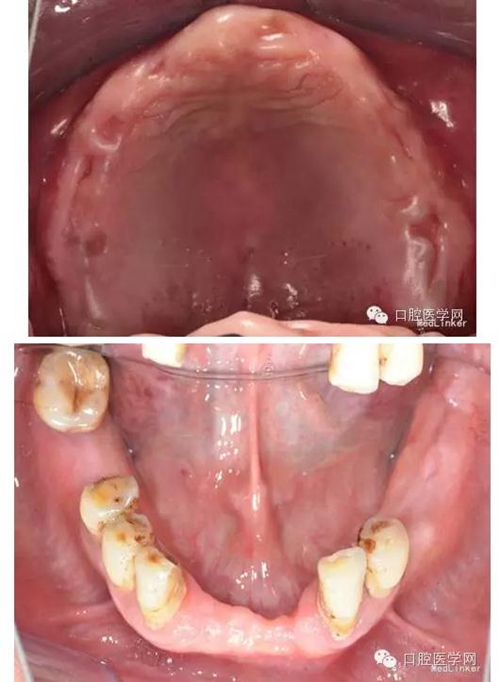

2、口內(nèi)檢查:口腔衛(wèi)生較差,PIL=2,CI=2;黏膜紅潤無潰瘍,厚度及移動(dòng)度正常;唇頰系帶附著正常、腭穹窿形態(tài)正常;唾液分泌正常。上頜無牙頜,牙槽嵴較豐滿,右上術(shù)區(qū)愈合良好,無尖銳骨棱、骨刺,未見明顯倒凹。#35-#38、#32-#42及#46、#48缺失,牙槽嵴無明顯吸收;#33#43伸長約2mm,叩(-),松(-);#46近中傾斜,叩(-),松Ⅰ度,#34頰側(cè)頸部楔狀缺損,未探及敏感,叩(-),松Ⅰ度;#33#34 及#43-#45,牙齦萎縮,he面嚴(yán)重磨耗,叩(-),松(-)。